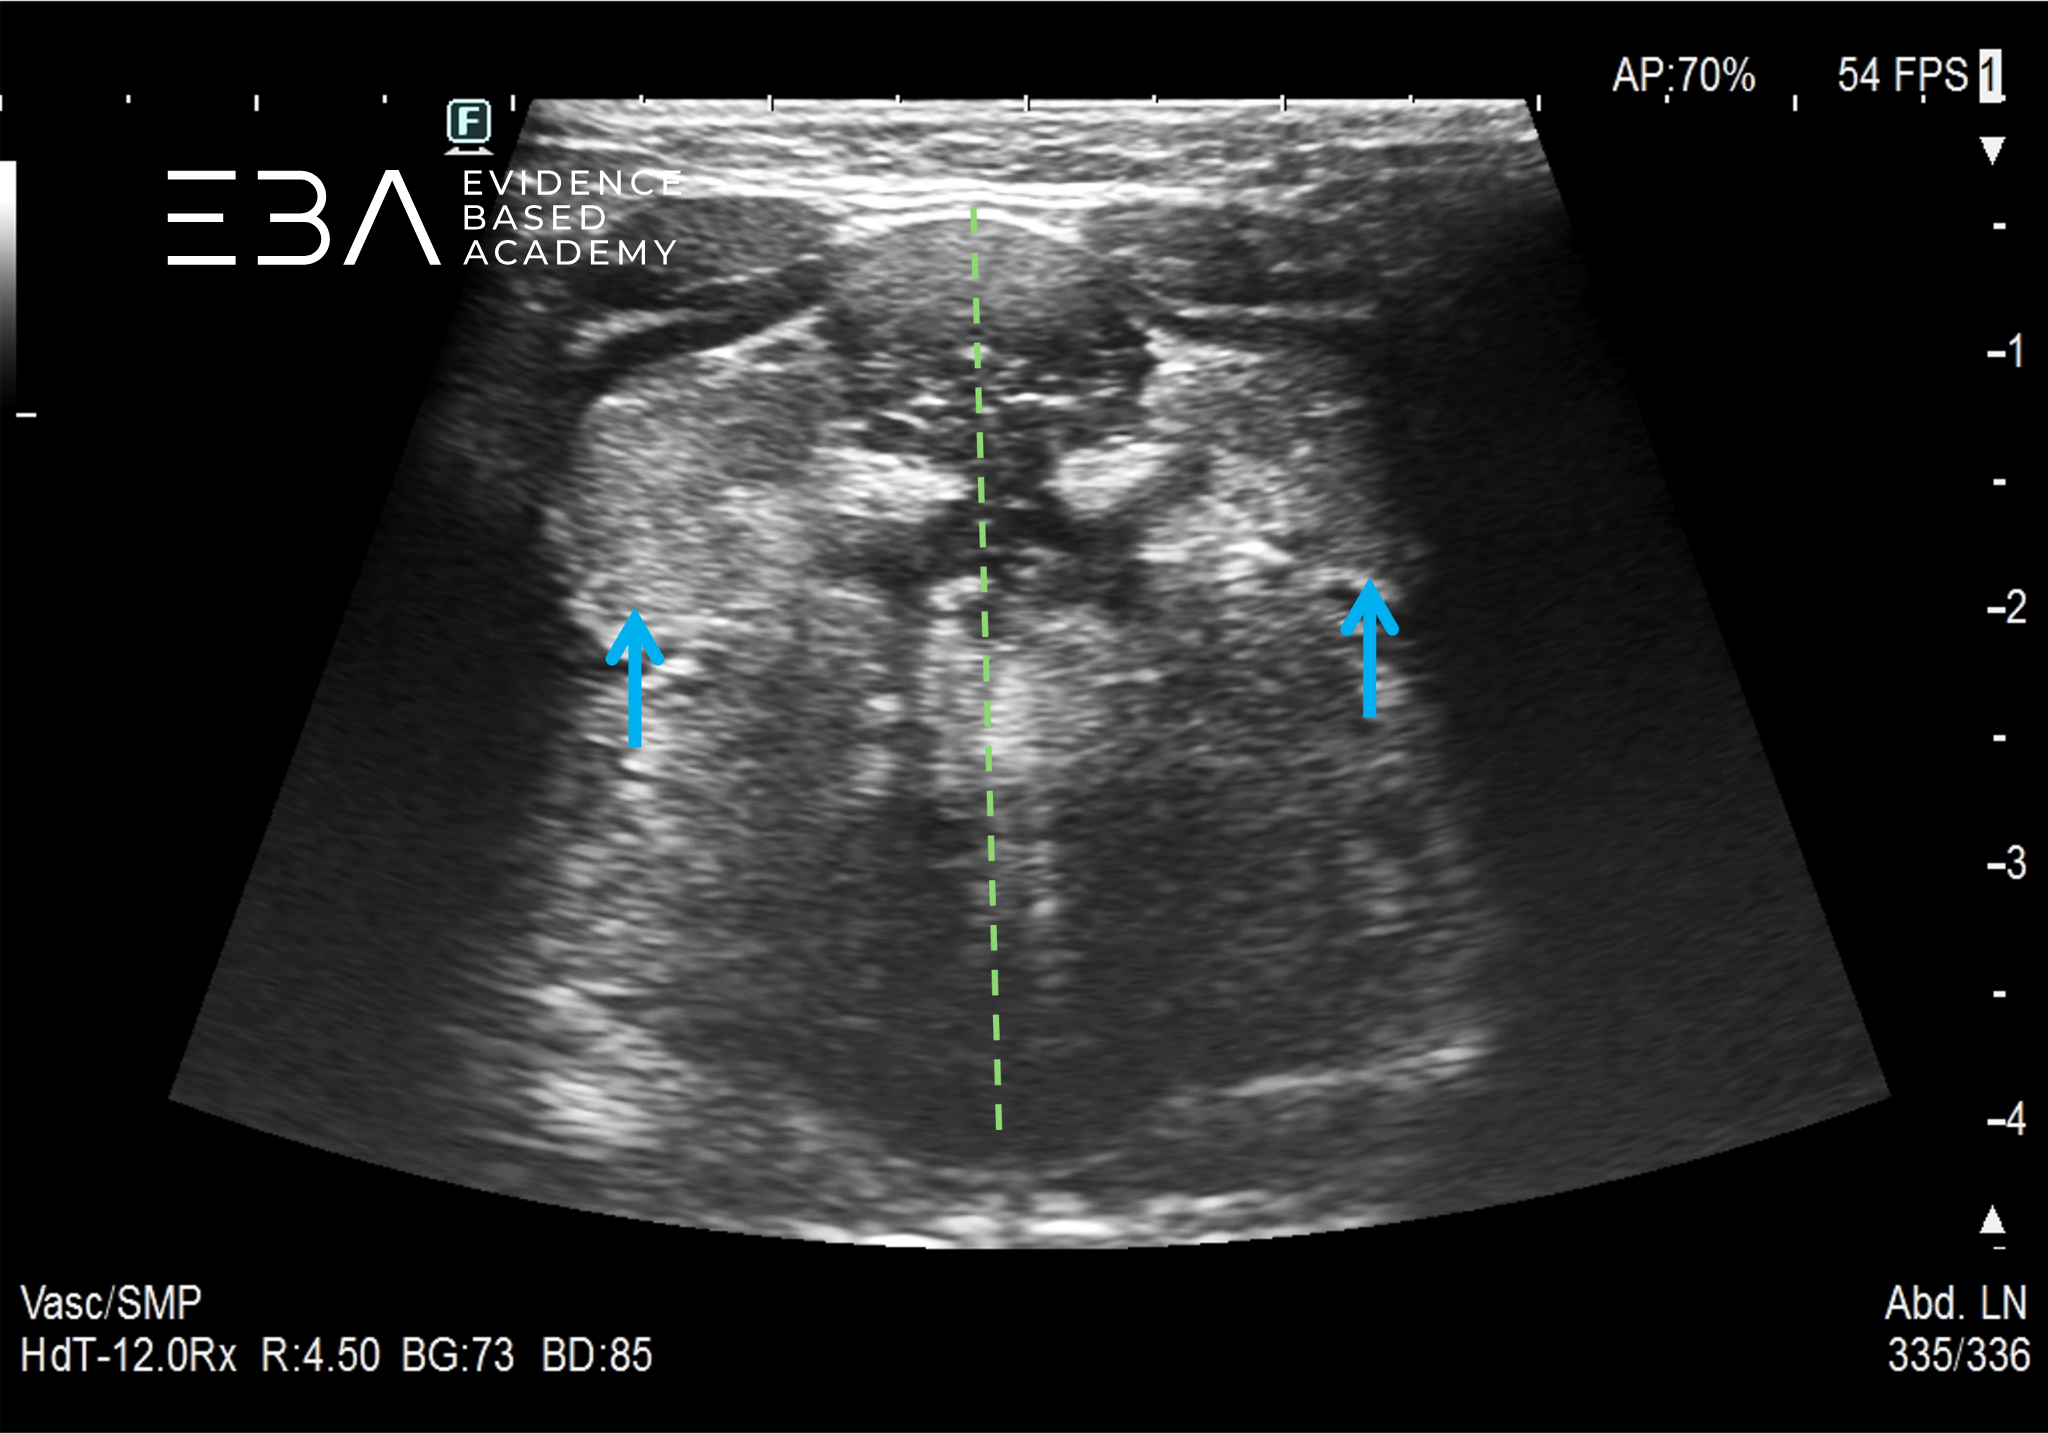

13. Ślinianki podjęzykowe (niebieskie strzałki) w projekcji poprzecznej, podbródkowej. Zieloną linią oznaczono linię pośrodkową ciała.